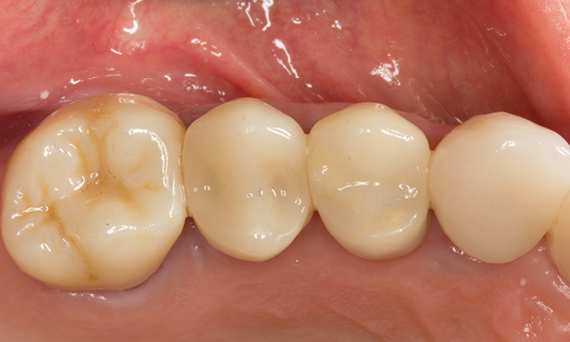

Before

Fractured ceramic restoration made from a leucite-reinforced glass-ceramic after a clinical service time of 12 years.

After

Chairside-fabricated restoration made from an advanced lithium-disilicate ceramic CEREC Tessera.